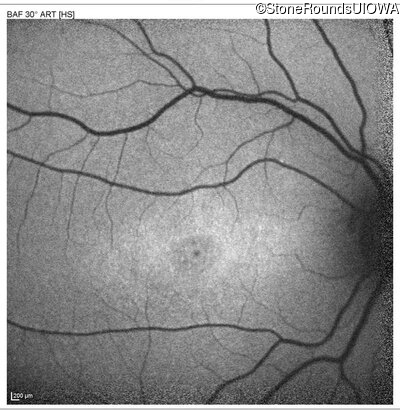

AR Stargardt Disease (IIA)

Age at visit:

14 years

OD

OS

20/32

20/20 -2

AR Stargardt Disease

ABCA4

Gly607Arg GGG>AGG

Gly1961Glu GGA>GAA

AR